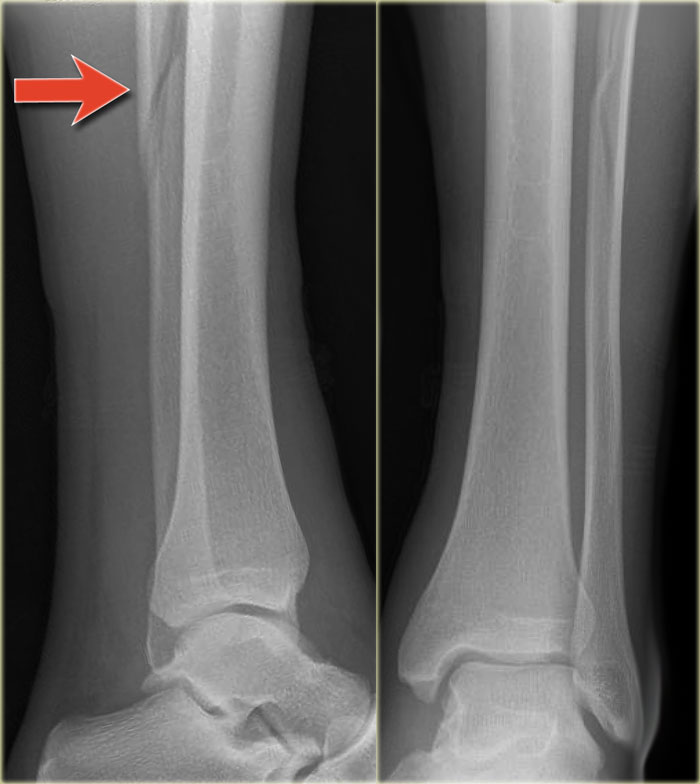

Example 3

In this case no fracture is seen, but only soft tissue swelling on the medial side.

In such a case, you have to rule out a Maisonneuve fracture, which is a high Weber C fracture.

Additional x-rays of the lower leg were taken.

There is a high fibula fracture.